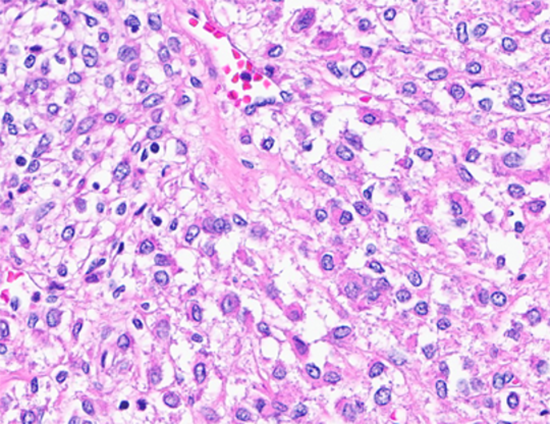

Figure 4: Tumor cells with clear cytoplasm. (Hematoxylin and Eosin stained (40x)